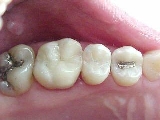

Caso 4

ANTES DEPOIS

Substituição de restaurações em amálgama de prata por resina composta no segundo pré-molar e por ONLAY ARTGLASS no primeiro molar.